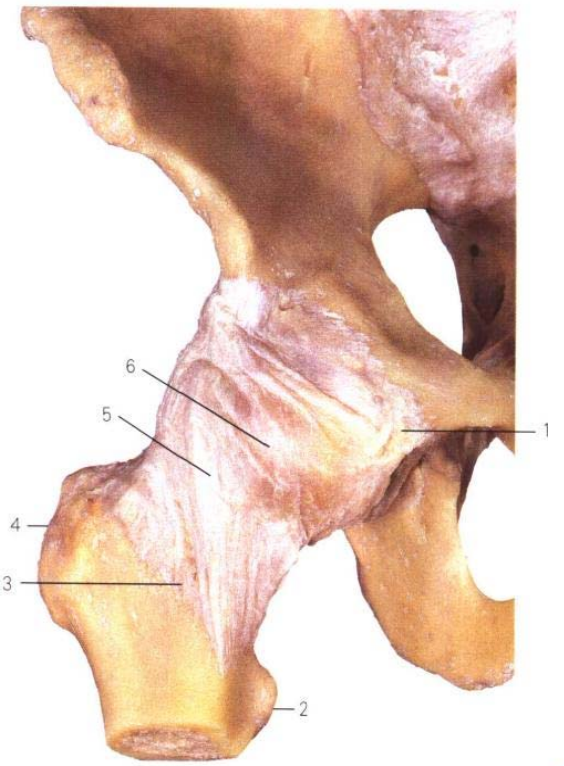

作为老年患者最常见的损伤,股骨颈骨折(SHF)是髋关节周围、股骨近端骨折的一种特殊形式。根据定义,骨折线位于股骨头和转子区域之间。因此,股骨颈骨折的骨折线不会延伸至转子区域。股骨颈骨折在解剖学上与经转子骨折和转子下骨折区分开来。血管灌注对于骨性愈合和股骨头的保留至关重要。除了旋股血管(旋股外侧动脉和旋股内侧动脉)外,关节囊内的支持带血管(“Wettbrecht支持带”)对股骨头的血管供应非常重要。其中,外侧滑膜皱襞尤为重要,它容纳上支持带动脉,在髋关节手术入路中必须予以保护。由于这种特殊的血管供应,个别情况下,即使在移位骨折中,股骨头的血供也可能得以保留。

A. 前面观: 1耻骨韧带 ,2小转子,3转子间线,4大转子, 5髂股韧带,6关节囊

B. 切开:7. 髋臼唇 ,8. 股骨头韧带 ,9. 股骨头,10. 轮匝带,11. 髋臼横韧带

C.后面观:12.股骨颈 ,13.坐股韧带

髋关节的稳定性依赖于髂股、耻股和坐股韧带,而股骨颈骨折可能破坏这种稳定性。因此,股骨颈骨折的治疗需要综合考虑解剖结构、血供和力学因素,以优化愈合过程和功能恢复。